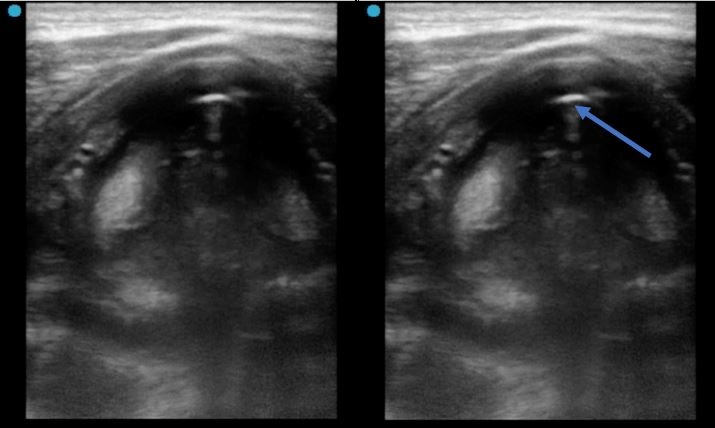

En la figura 5, con manguito hinchado, se observa el artefacto de gas (flecha azul) correspondiente al tubo endotraqueal a nivel de la glotis.